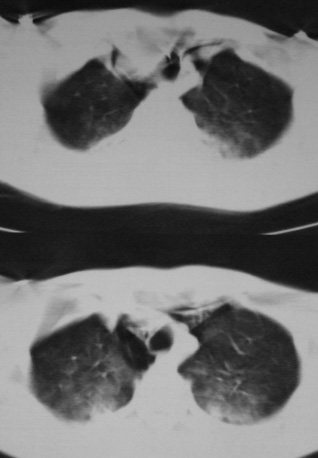

男,18岁,车祸20小时后胸ct.血氧饱和度80,呼吸45次/分.

1:双肺挫裂伤,以双下肺明显。

2:纵隔气肿

1.双肺挫伤,2.纵隔积气。注意右侧主支气管是否有断裂?